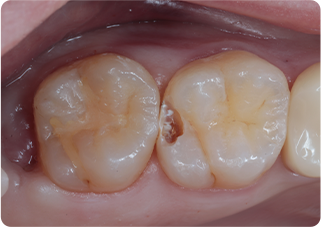

精密根管治療①

術前

| 主訴 | 奥歯で噛むと痛い |

| 治療期間/回数 | 1ヵ月、3回 |

| 価格(税込) | 88,000円(税込) |

| リスク・副作用 | 病変再発、歯根破折の可能性 |

| ポイント | う蝕検知液を用い、むし歯の取り残しが無いようにし、ラバーダム防湿を行い、無菌的に根管治療を行った。根管充填材は、殺菌作用の強い保険適応外のMTAセメントを使用した。 |